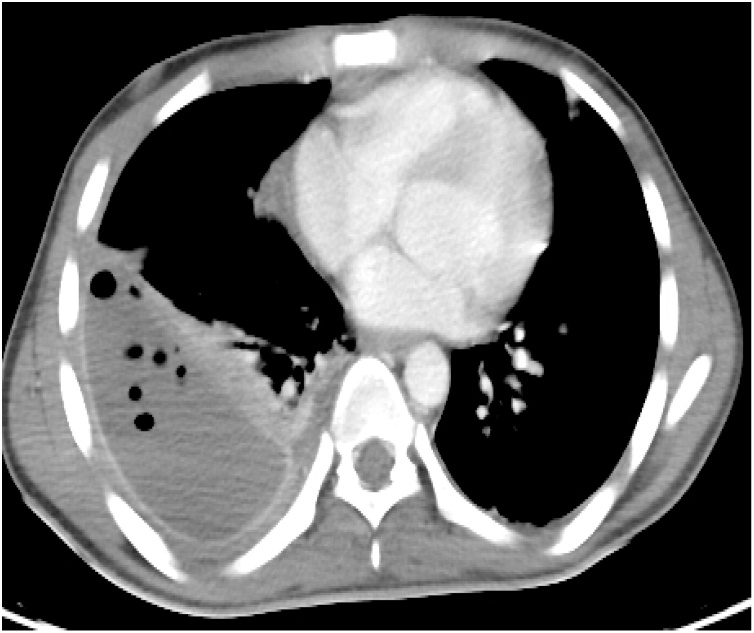

As the right-sided pleural effusion had transformed into a well-formed empyema, decortication was performed (Fig. 7). Eight weeks after admission, the patient was discharged home. He was followed up for one year; no late complications were encountered. Follow up CT showed normal looking both lung and liver parenchyma with no evidence of recurrence of the IHPA (Fig. 8).

Fig. 7.

CT Chest shows the well-formed right sided empyema.